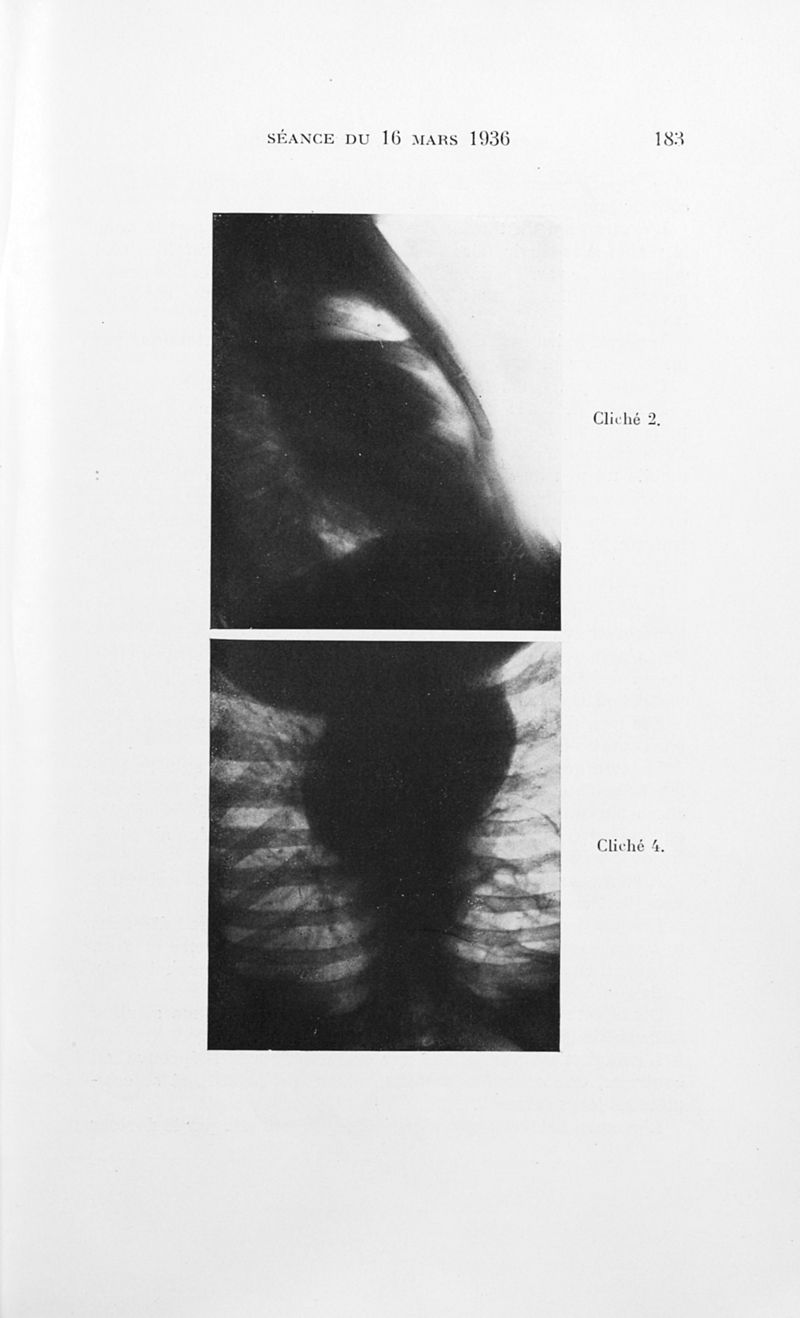

Bulletins de la société de pédiatrie de Paris

Tome trente-quatrième. - Paris : Masson et Cie, 1936.